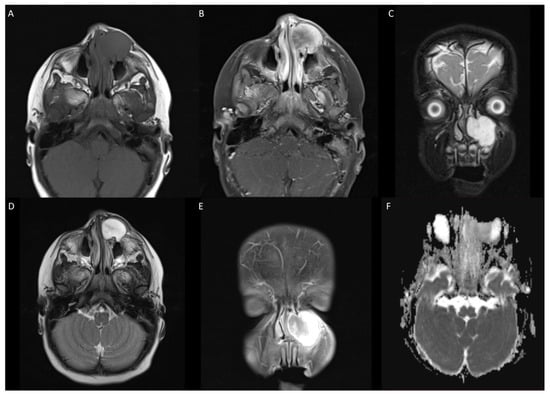

3.2. Case 2